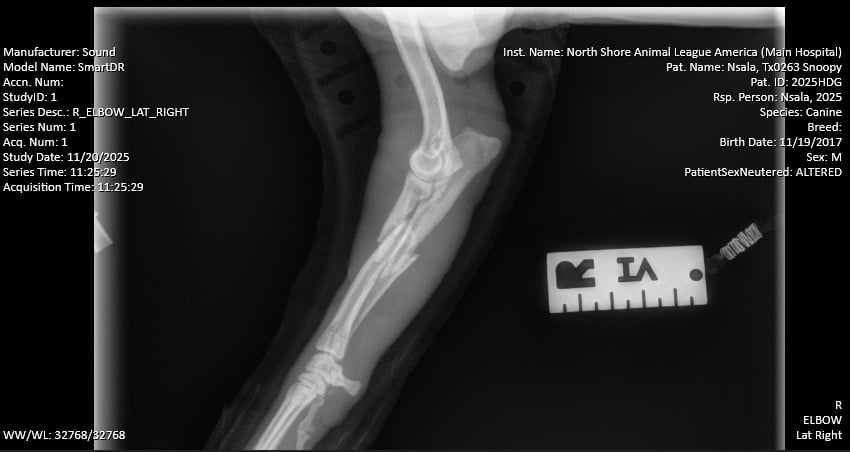

Snoopy, a two-year-old hound mix, arrived wearing a splint. X-rays revealed, however, that the splint was doing more harm than good. “His radius and ulna were completely fractured, and the bones inside the splint had shifted,” said Dr. Verdino. “If left to heal that way, the leg would have ended up several centimeters shorter and completely nonfunctional. Ultimately, it would have been amputated.” Instead, Snoopy underwent surgery to stabilize the limb. “We placed a metal plate and screws on the radius and a small pin on the ulna. Surgery went well, and he’s already weight-bearing. His long-term outlook is excellent.”